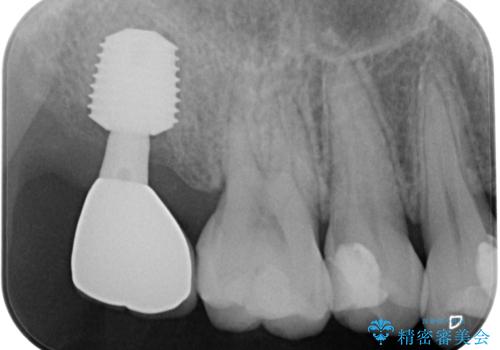

抜歯後に不快感は消失したのですが、手前の歯にあるむし歯が痛み出してきたため、セラミックインレーにて修復治療を並行して行いました。